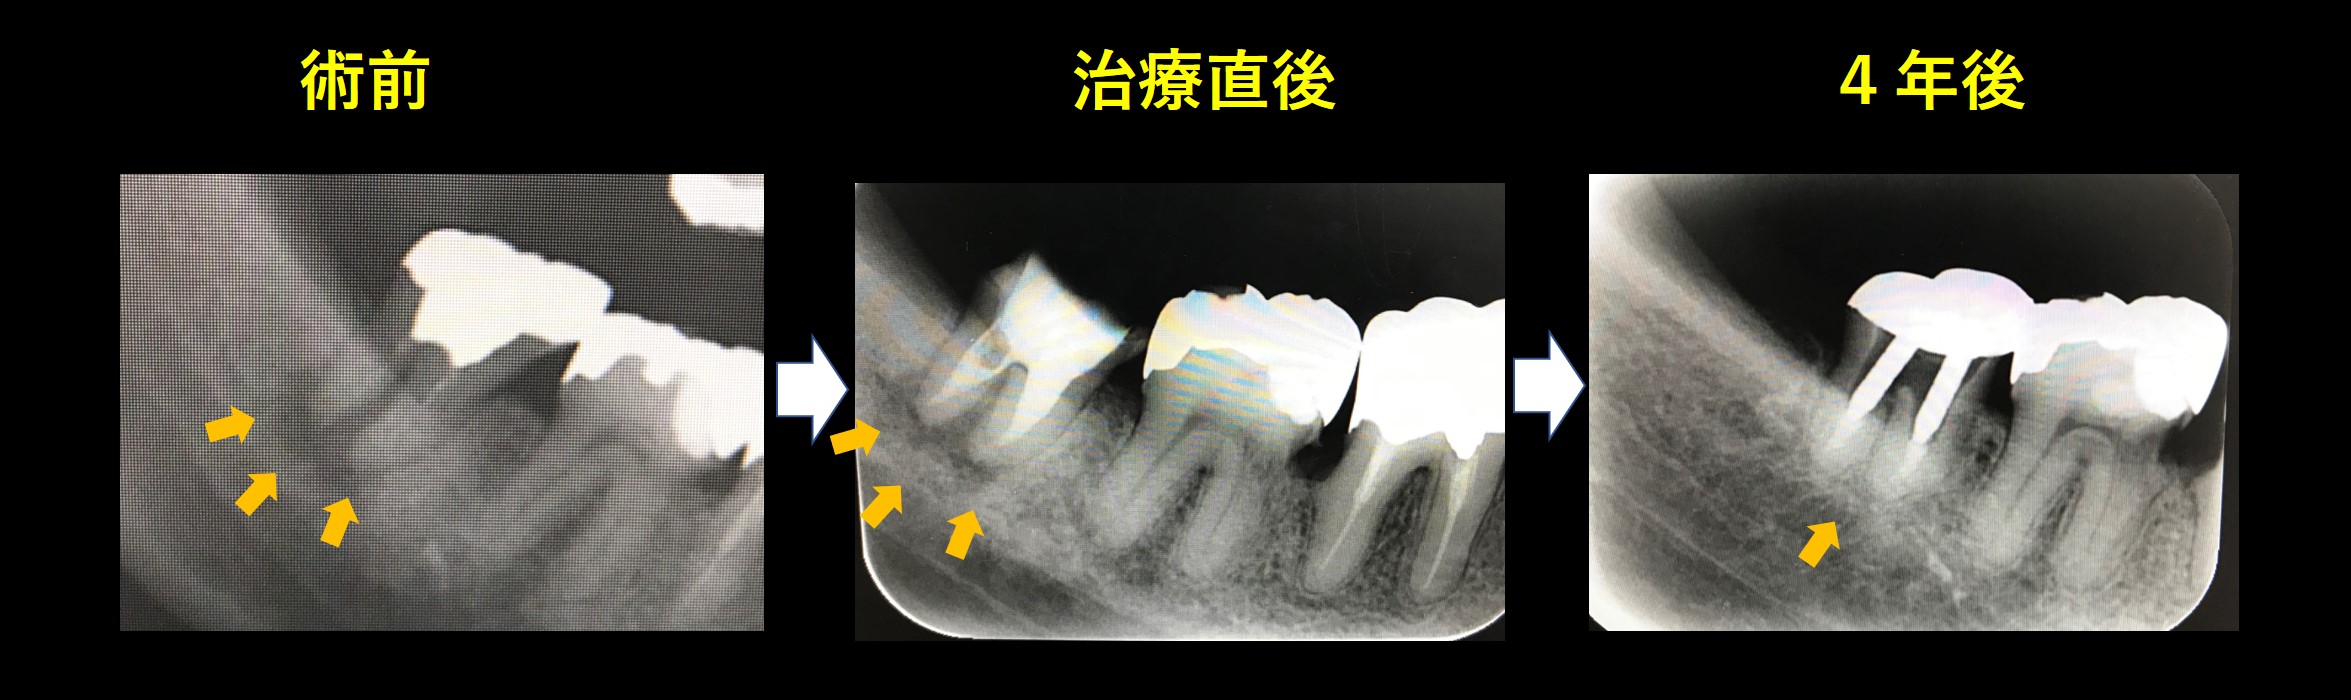

レントゲン写真です。

左が術前、歯茎の腫れおよび動揺が確認されました。矢印部分に黒い影が見られます。根の先の骨が感染で溶けています。

右が根管治療後です。歯茎の腫れ、動揺も改善し、レントゲン上で矢印部分の骨の再生が確認できます。